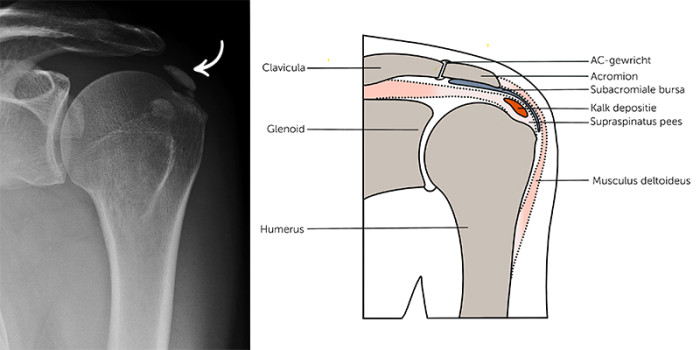

Tachtig procent van de mensen die met schouderklachten de huisarts bezoeken heeft een subacromiaal pijnsyndroom (SAPS). Patiënten hebben pijn in de schouder en/of een bewegingsbeperking in het abductietraject, die wordt veroorzaakt door een aandoening van de rotator cuff en/of bursa onder het schouderdak (acromion). Een belangrijke veroorzaker van SAPS is de combinatie van een ontstoken rotatorcuffpees en kalkafzetting in de aangedane pees, ook wel bekend als calcificerende tendinopathie of tendinitis calcarea. De uitdaging is om te bepalen in welke fase van de ziekte de patiënt zich bevindt en hier de behandeling op te laten aansluiten.